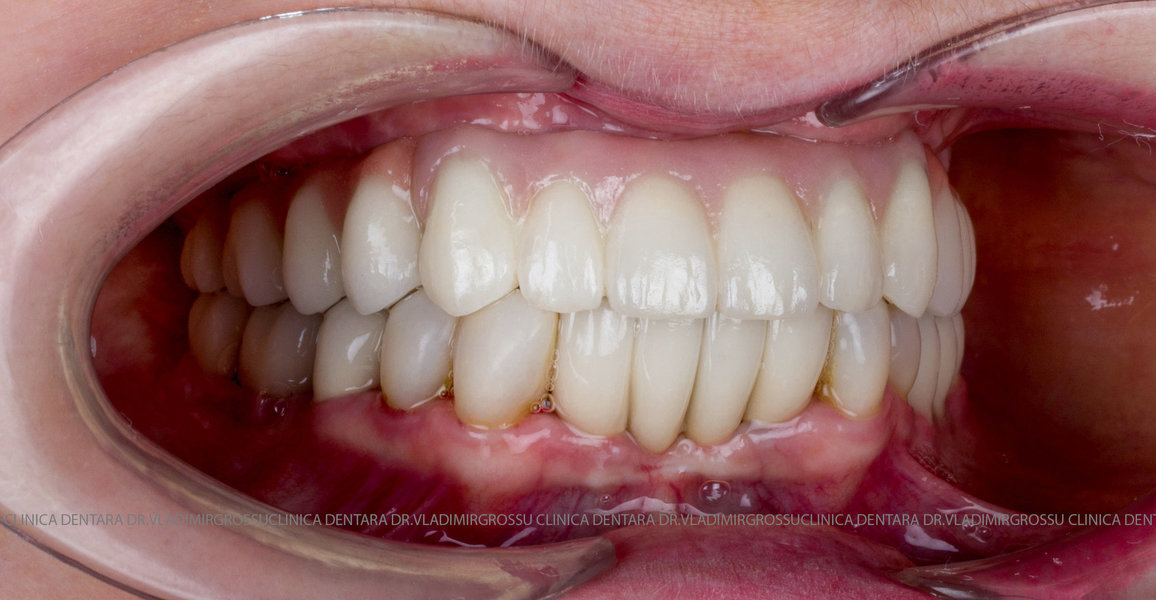

Cazuri clinice conceptul All-on-6